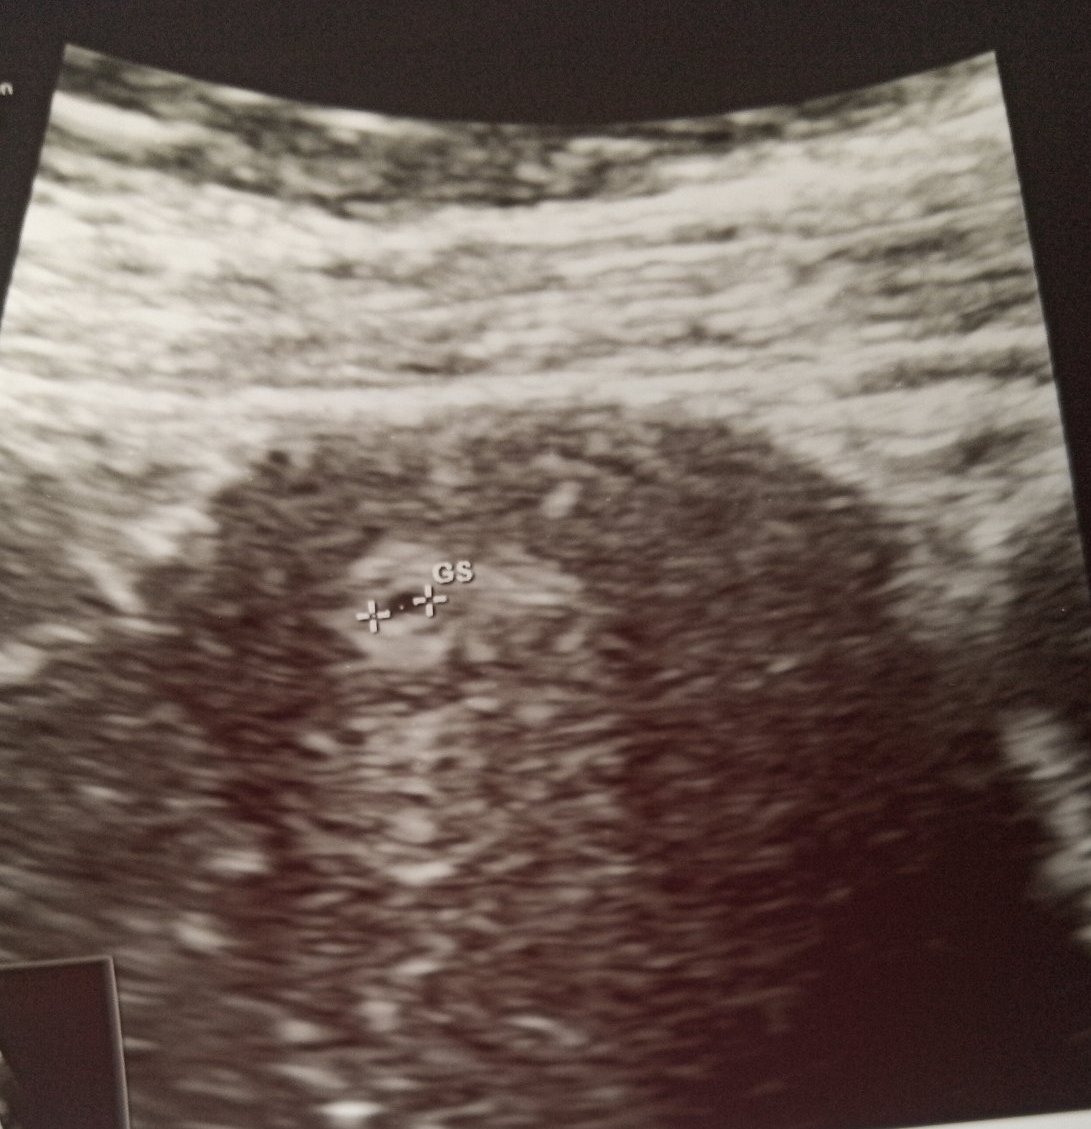

Дидката90, в такъв случай ЧХГ е много ниско за такова закъснение. Вече трябва да се види и плоден сак. Има вероятност да е извънматочна бременност. Лекарят ще ти каже как ще процедирате оттук насетне.

Днес се водя една точка,но не е много сигурен

Расте бавно, така че бих те посъветвала след седмица пак на преглед. Тогава ще се види дали точката наистина е плоден сак и дали е нараснал от тогава. По принцип ЧХГ е само ориентир. Най-важното е какво се вижда на ехограф.

Сега в сряда следобед съм на доктор,ще видим,какво става.